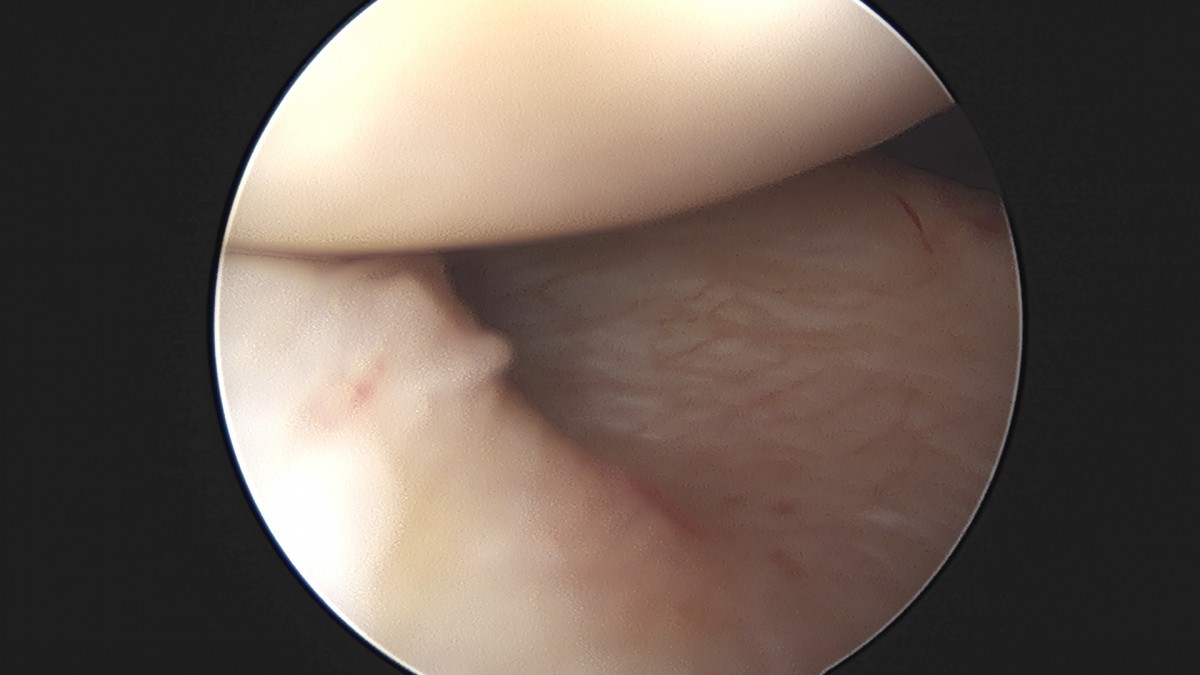

이재상원장님 어깨 석회 제거술 조광O 환자

dae765e4d9ac96aee867c9d6292d8784_1758004692_5451.jpg